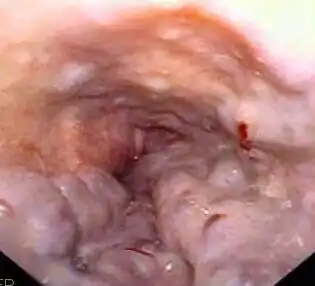

| Imagem microscópica de um fígado com cirrose, causa mais comum de síndrome hepatorrenal. | |